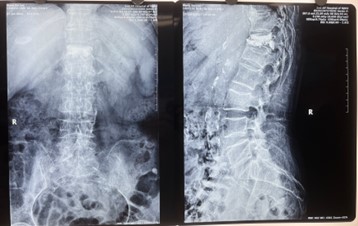

對比一些9英寸的平板C形臂,普愛醫(yī)療PLX119C大平板C形臂,30CM*30CM想(30CM*30CM)的成像范圍,一次性可成像5節(jié)腰椎,有效減少小視野C形臂難以一次性確定傷椎,可能需要進行多次拍攝的問題,使得手術效率更快、更準確。